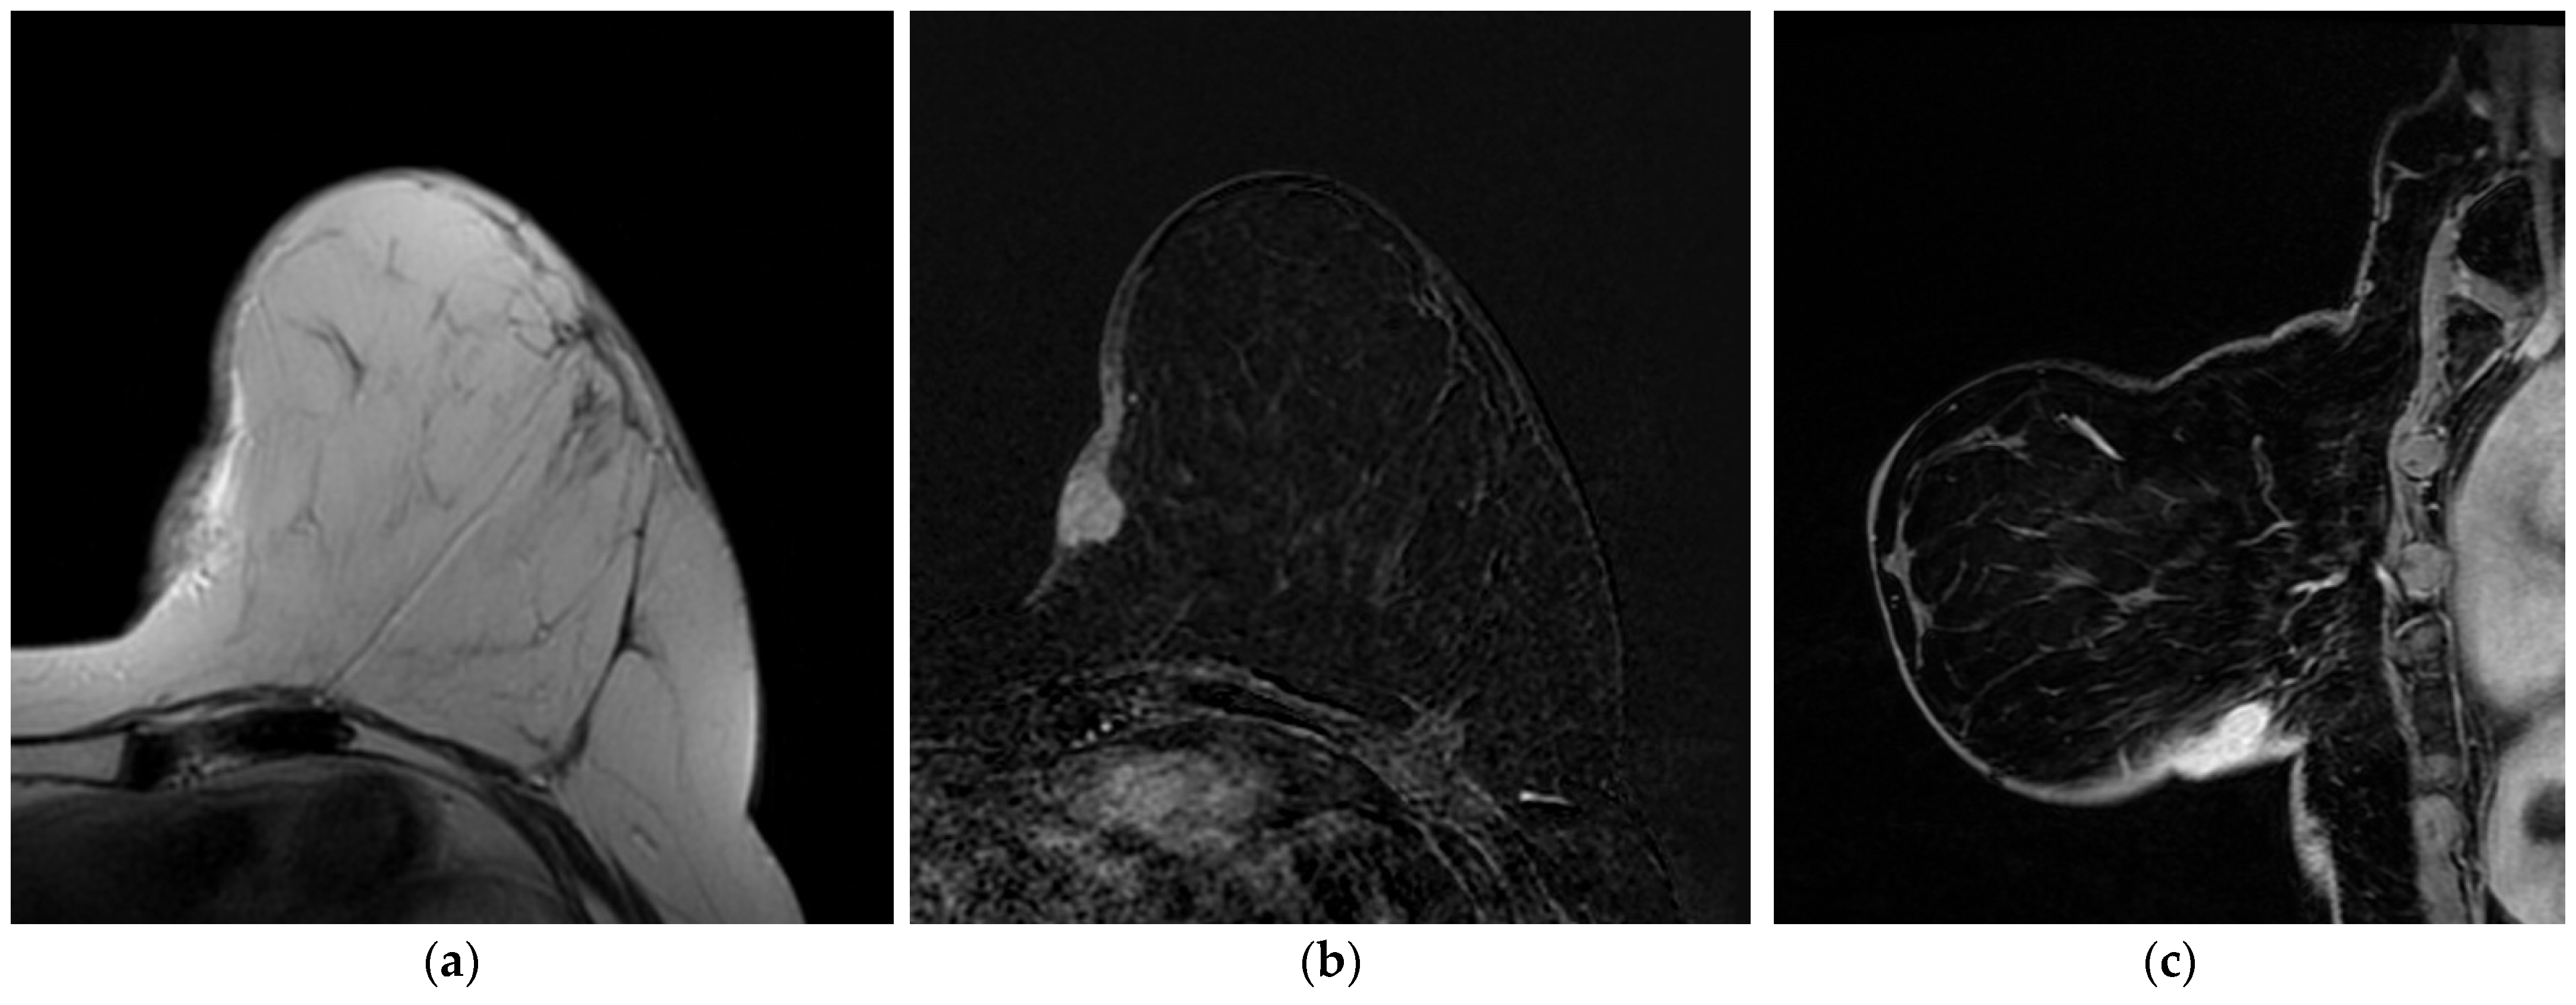

4.3. Magnetic Resonance Imaging